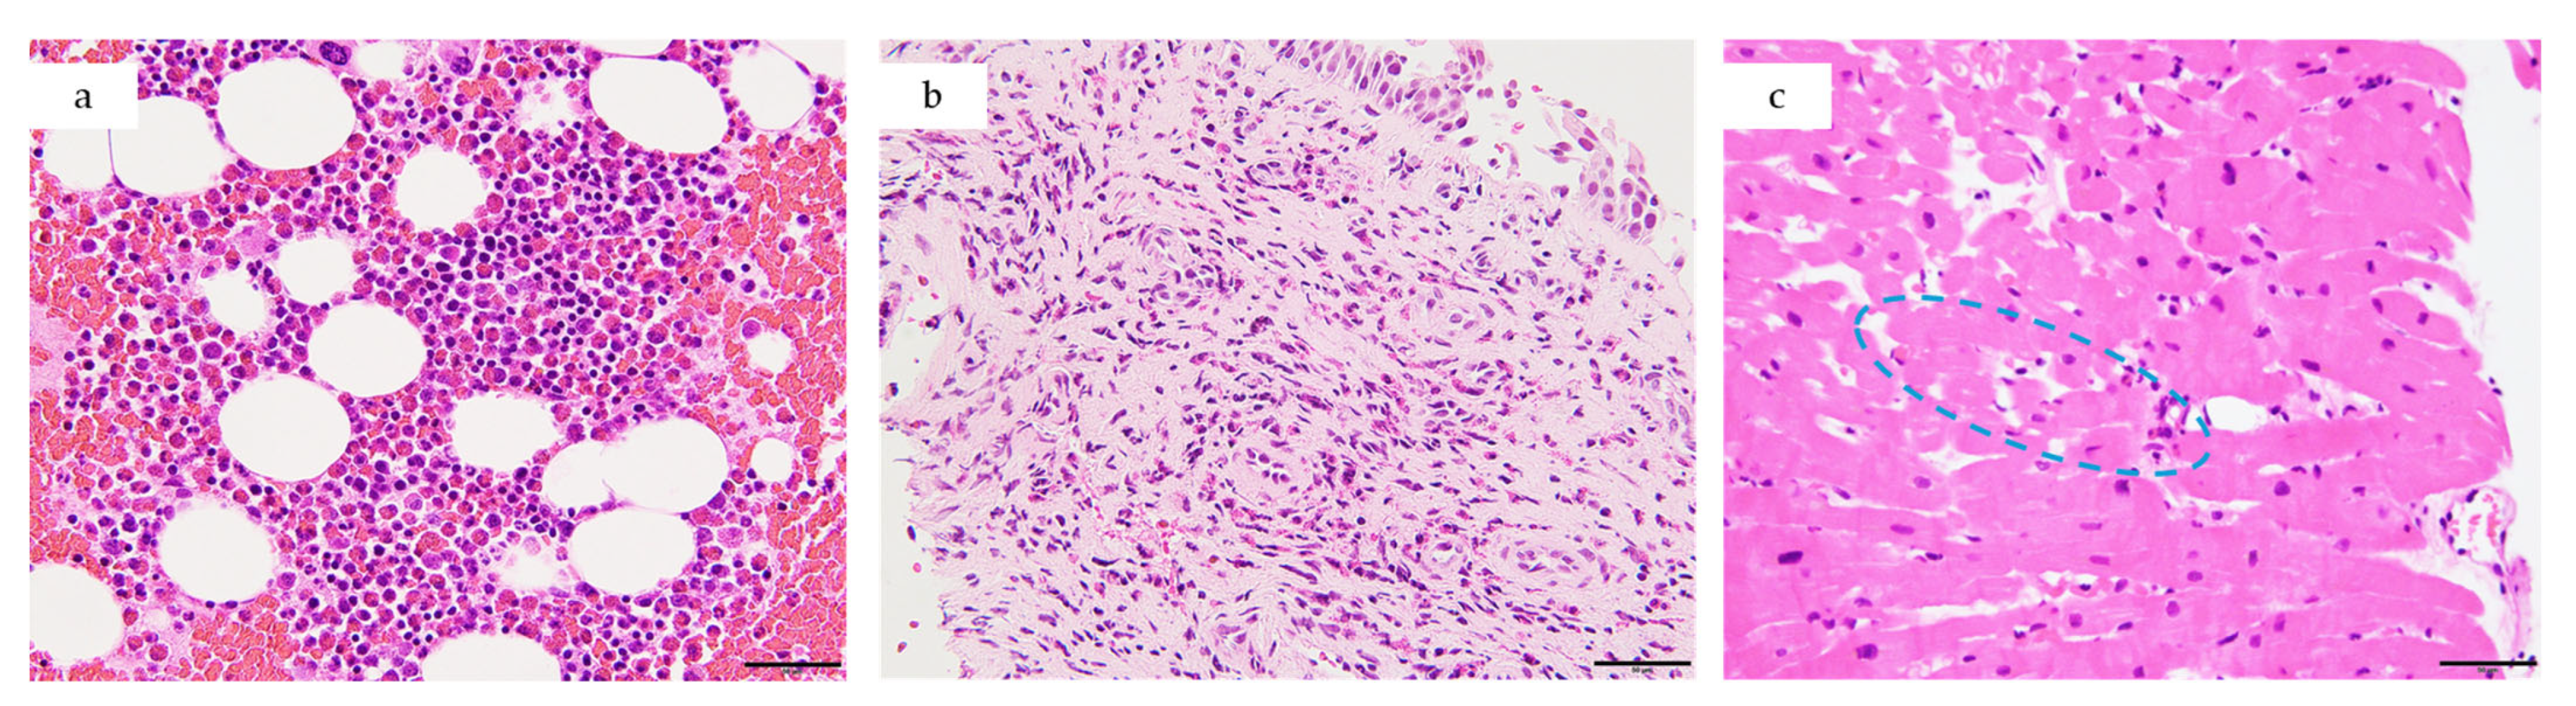

| This case, 2025 | 24, M | Japan | ANCA-negative EGPA | 13,060 | Sinus, asthma, lung, bone marrow | EF 47%, myocardial edema (Figure 2c) → EF 59% (Day 15)|biventricular subendocardial enhancement (Figure 5) | Mixed lymphohistiocytic + eosinophilic infiltrates, no necrosis | Steroids → mepo (300 mg) | Day 4—Initial therapy | Steroid-sparing, EF improvement, clinical improvement—remission at 19 months |